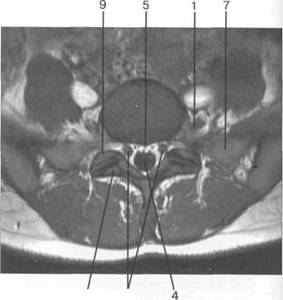

MPT. Cw_v.